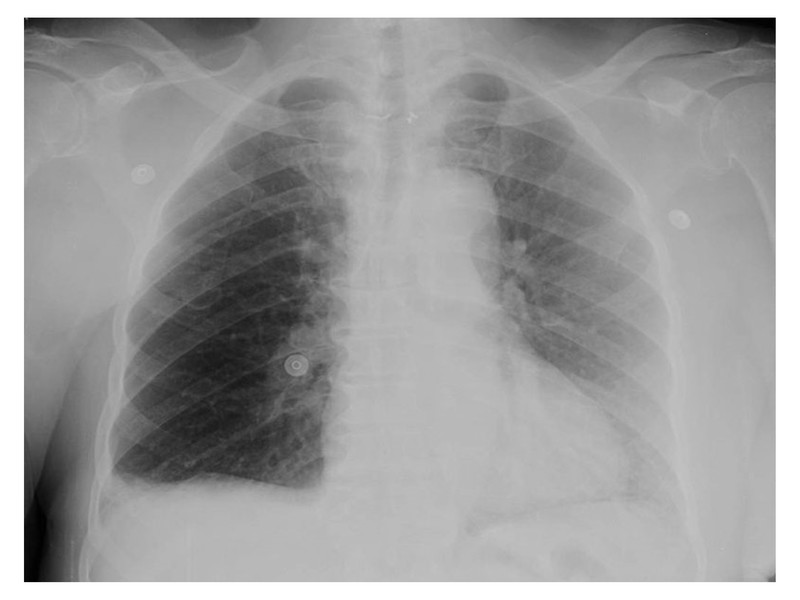

X-ray showed no cardiomegaly or pleural effusion but possible patchy areas of consolidation. Lab values revealed ↑Hb (18.2,) and some leucocytosis. ABG suggested mild respiratory acidosis. hsTroponin T was elevated. Simplified Geneva score for PTE was 3 but d-dimer was at border-line.

X-Ray is another simple test which should have been more closely examined.

While there is no cardiomegaly or pleural effusion, on closer look several signs suggestive of pulmonary embolism are present;

- Hampton’s hump; wedge-shaped, pleural-based consolidation seems present

- Westermark sign; oligemia in right lower lung field is present

- Fleischner sign; central pulmonary artery seems prominent

In our case, the clinical image of a pulmonary embolism was ambiguous, making it difficult to propose an exact diagnosis at an early stage. Moreover, presences of possible ST-segment elevation, a positive Troponin T test and –ve D-dimer test mislead us till coronary angiogram was done. Clinical probability score (Simplified Geneva Score of 3) should have alerted us right from the beginning the possibility of acute PE and combined with the ECG finding of negative T wave in lead III and V1 and X-ray signs like Hampton’s hump, Westermark sign and Fleischner sign along with echocardiographic appearance of RV dilatation should have clinched the diagnosis.